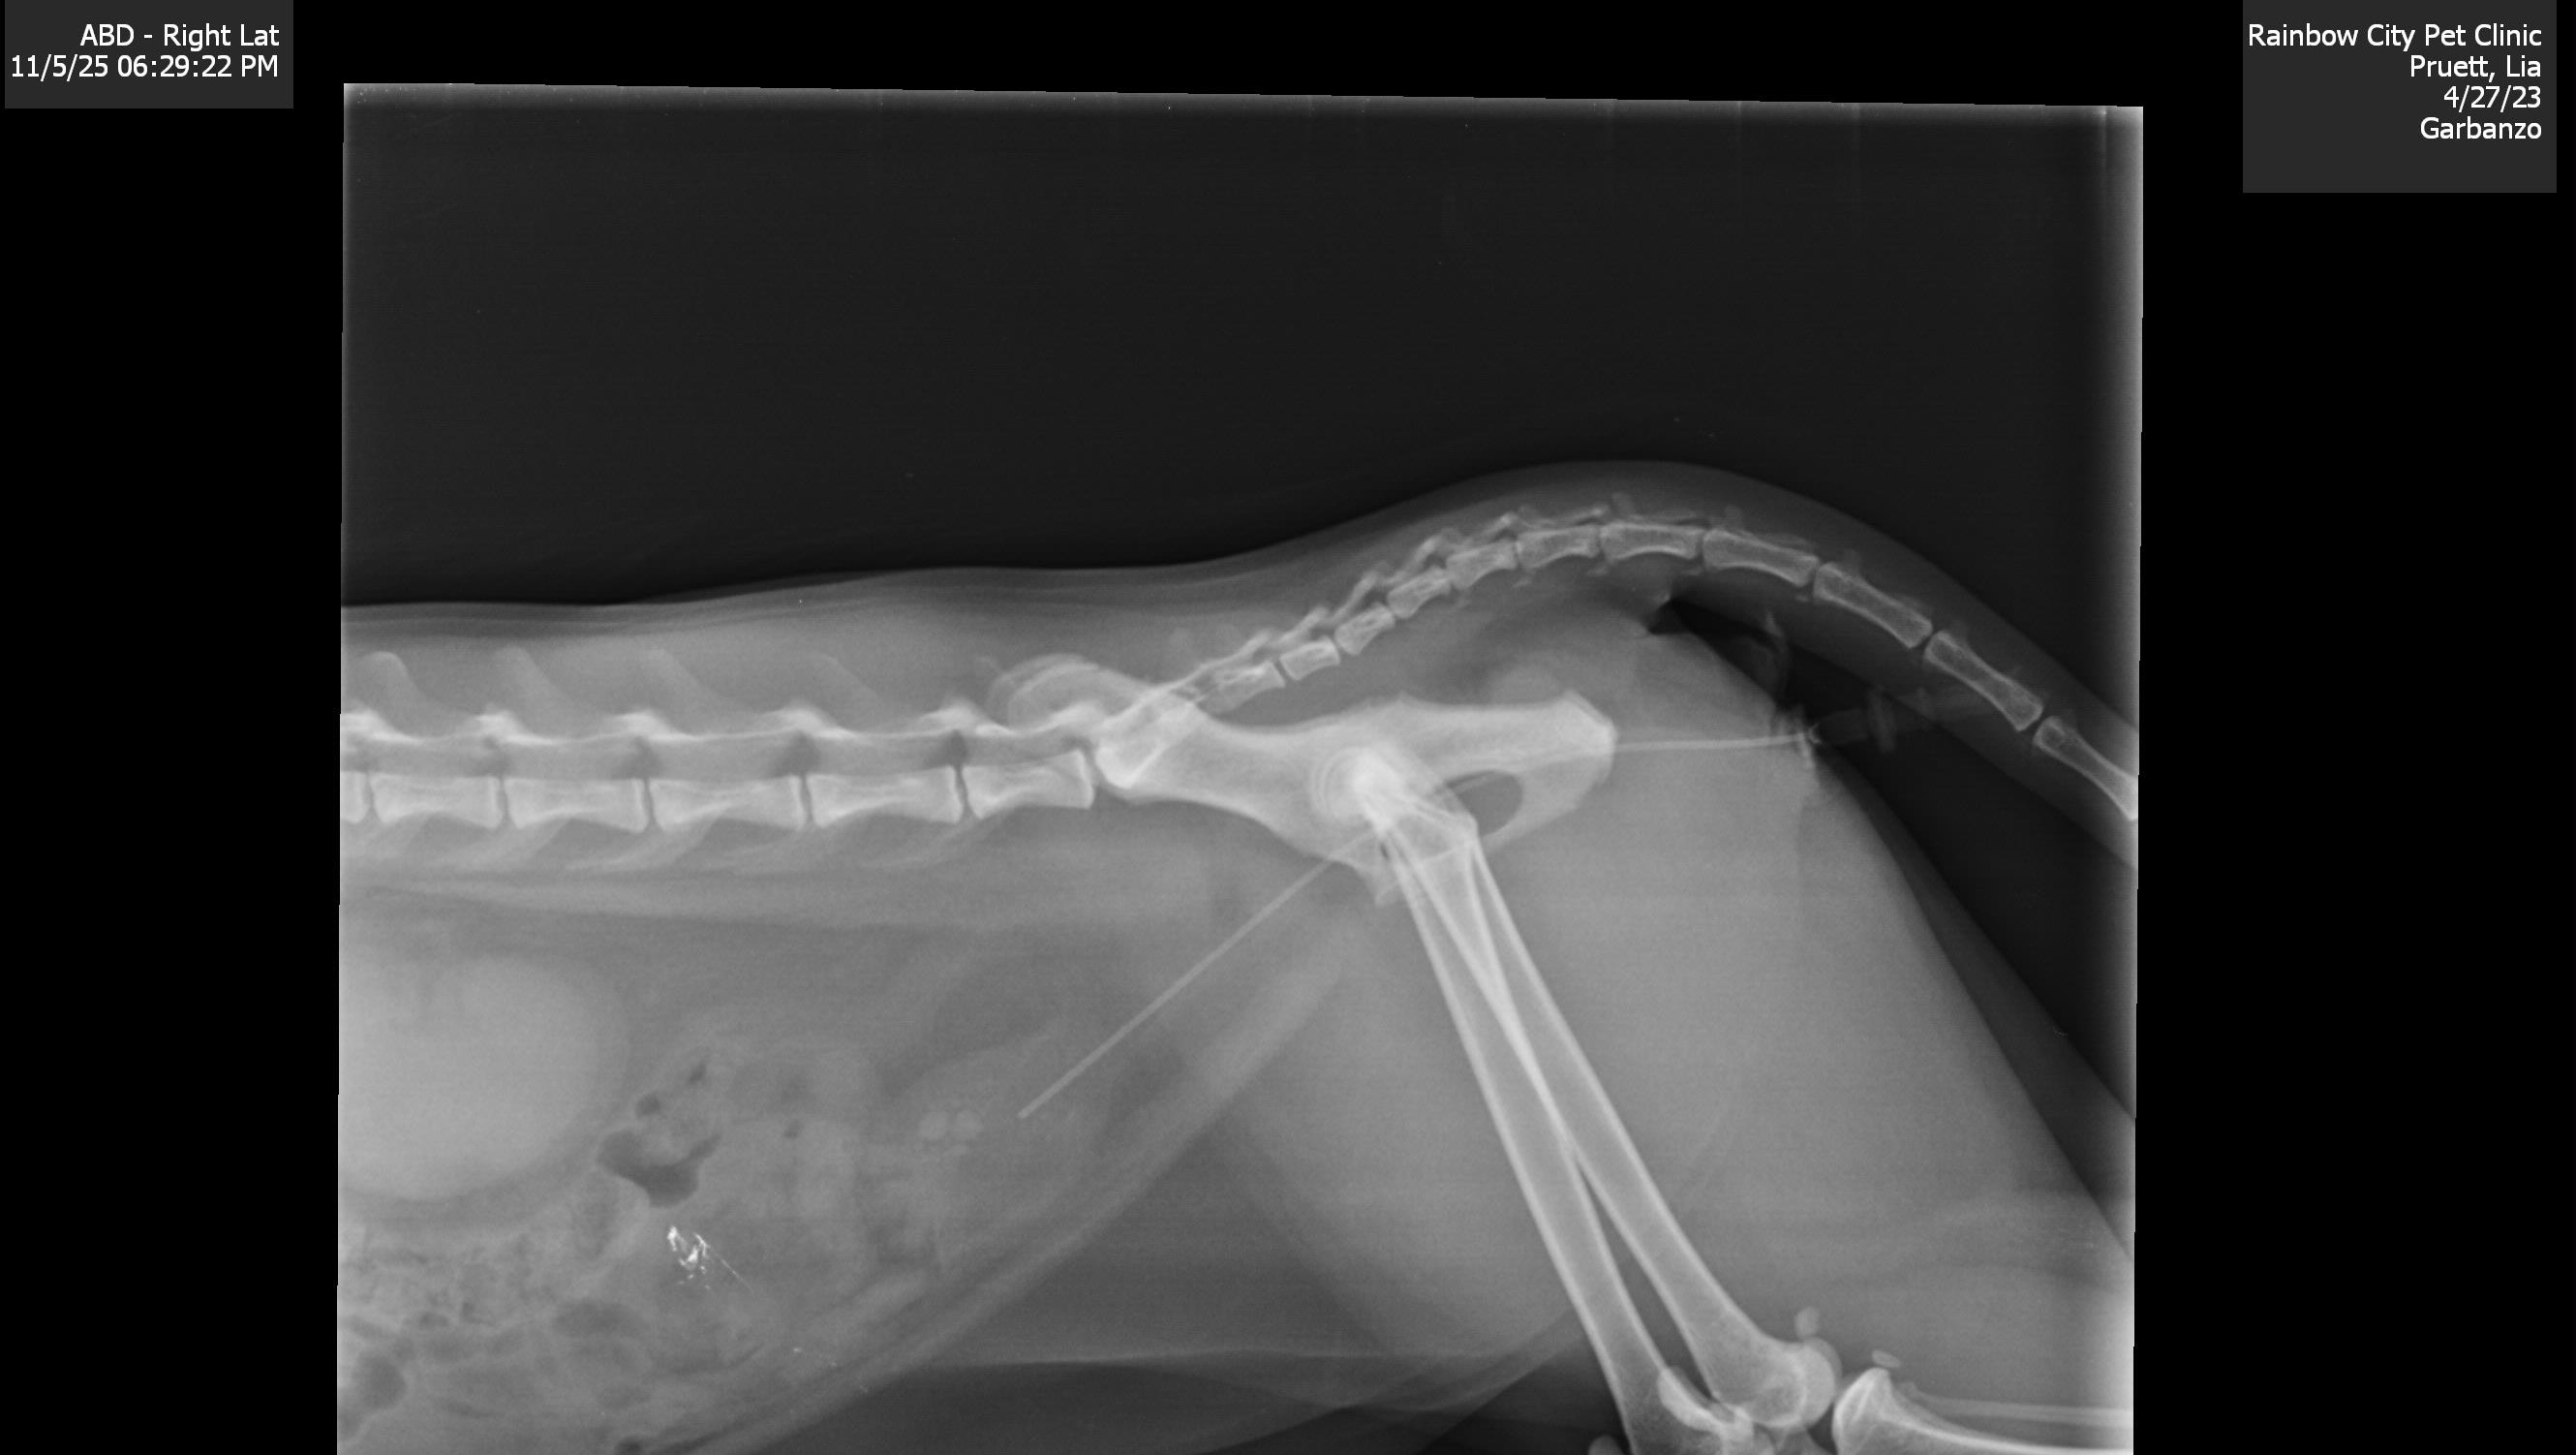

On Monday, November 3rd, Garbo went back to the vet. They discovered three stones in his bladder but assured us there was no immediate blockage. They prescribed antibiotics in hopes of them breaking them up on his own.

But by Wednesday, November 5th, Garbo's condition deteriorated drastically. He wasn’t moving, eating, or drinking. He seemed so weak and lethargic, it was heartbreaking to watch. I rushed him to the emergency vet at 2 a.m., and after a $300 emergency treatment, they drained his bladder, which was filled with bloodied urine. He was blocked.

His options are running out, and it’s looking more and more like he'll need surgery.

Surgery to remove the bladder stones.

A more drastic procedure called a Perineal Urethrostomy, which would permanently widen his urethra and allow him to urinate comfortably for the rest of his life.